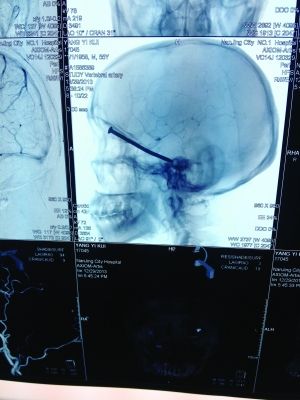

CT投影

CT投影結(jié)果,把大家嚇了一跳:楊先生腦子里居然有一根長(zhǎng)釘,從眼眶一直“伸”到了接近后腦勺的位置!鐵釘細(xì)長(zhǎng)略帶彎曲,長(zhǎng)達(dá)8厘米。根據(jù)推測(cè),鐵釘應(yīng)該是從上眼眶的縫隙中飛入,一直插進(jìn)腦顱中,末端還有一個(gè)小小凸出的釘帽。